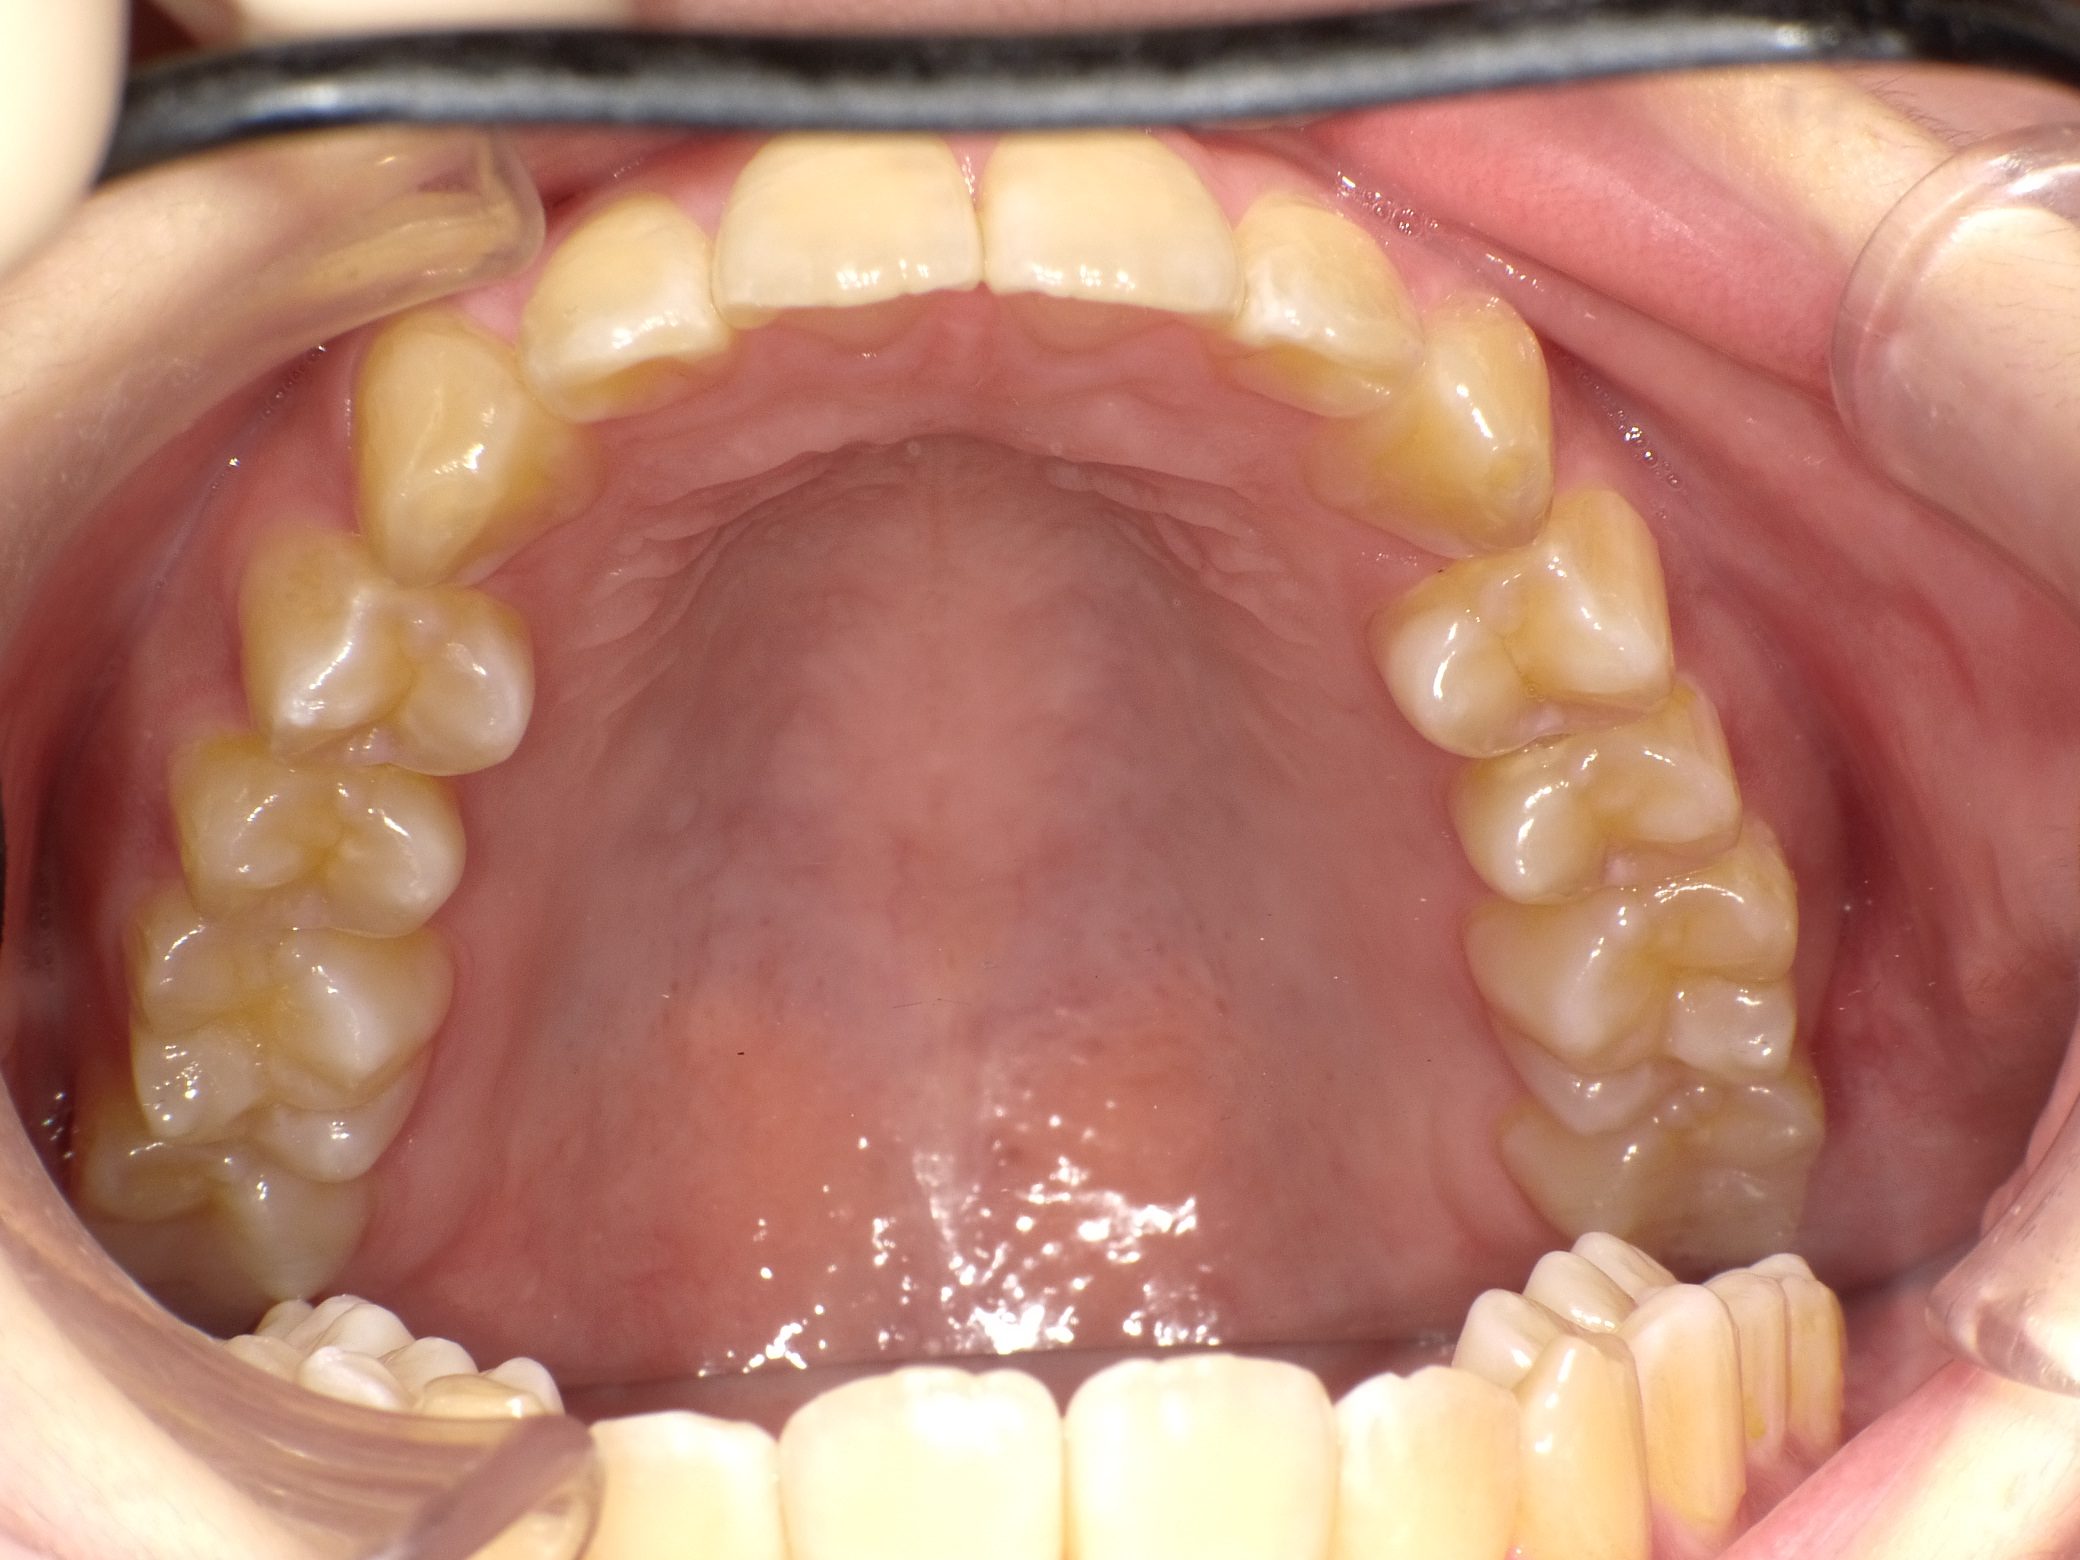

Before

After

【中学生】インビザライン矯正 叢生(ガタガタ)と上顎前突(出っ歯)を改善

でこぼこ

出っ歯

非抜歯

2期治療のみ